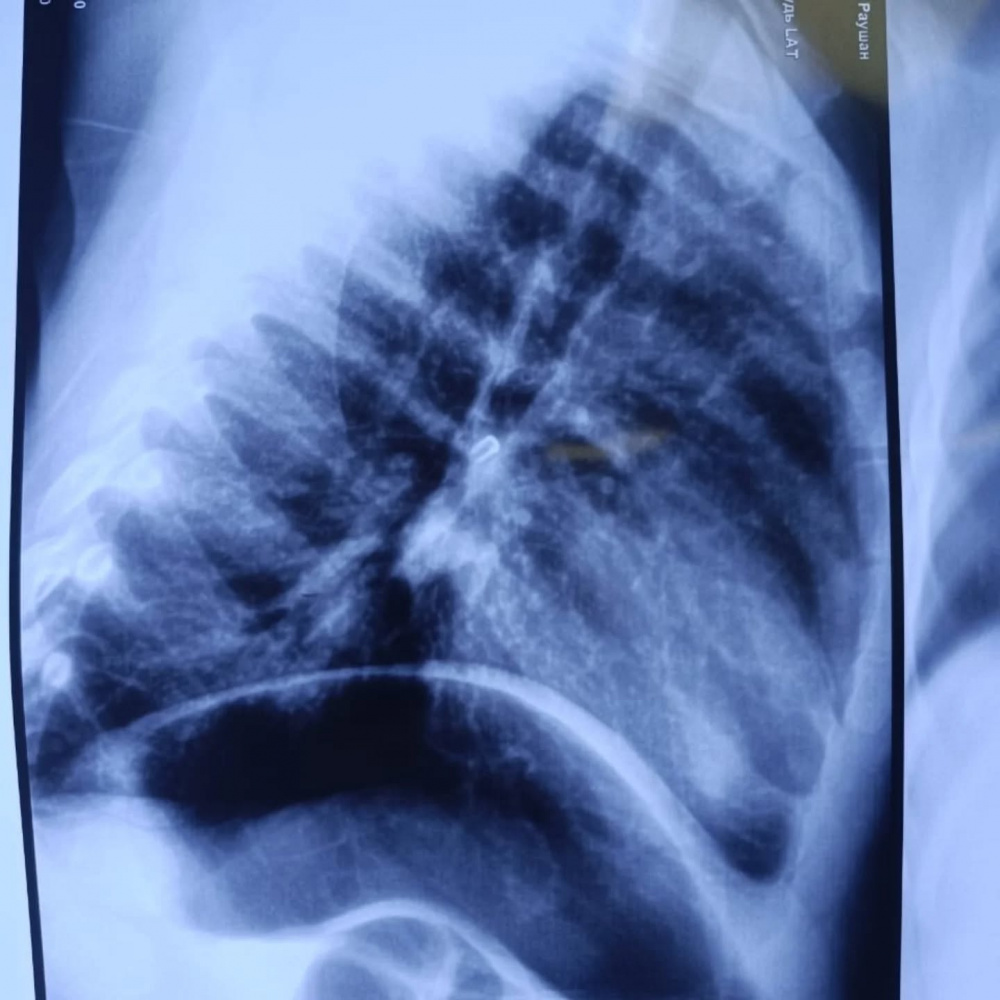

При поступлении, по информации медиков, состояние малыша расценивалось как тяжелое: у него была дыхательная недостаточность. Рентгенограмма выявила инородное тело в проекции правого главного бронха. Врачи провели ригидную бронхоскопию под наркозом с удалением инородного тела - бусины. Состояние ребенка на сегодня удовлетворительное, дыхание восстановлено.